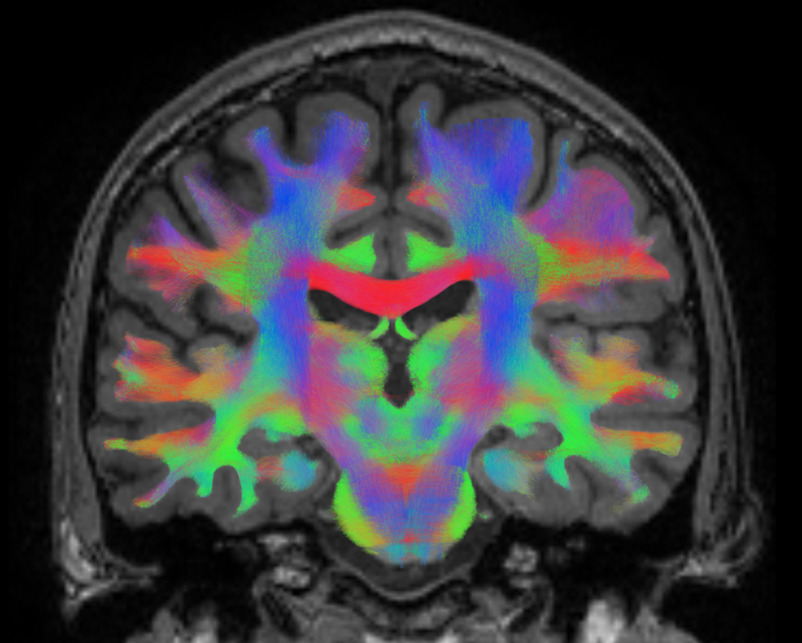

We can use another type of MR imaging to see the white matter tracts in the brain and how they connect the different brain regions together:

Brain 2.png

From: https://phys.org/news/2014-06-esa-image-space-brain-networking.html